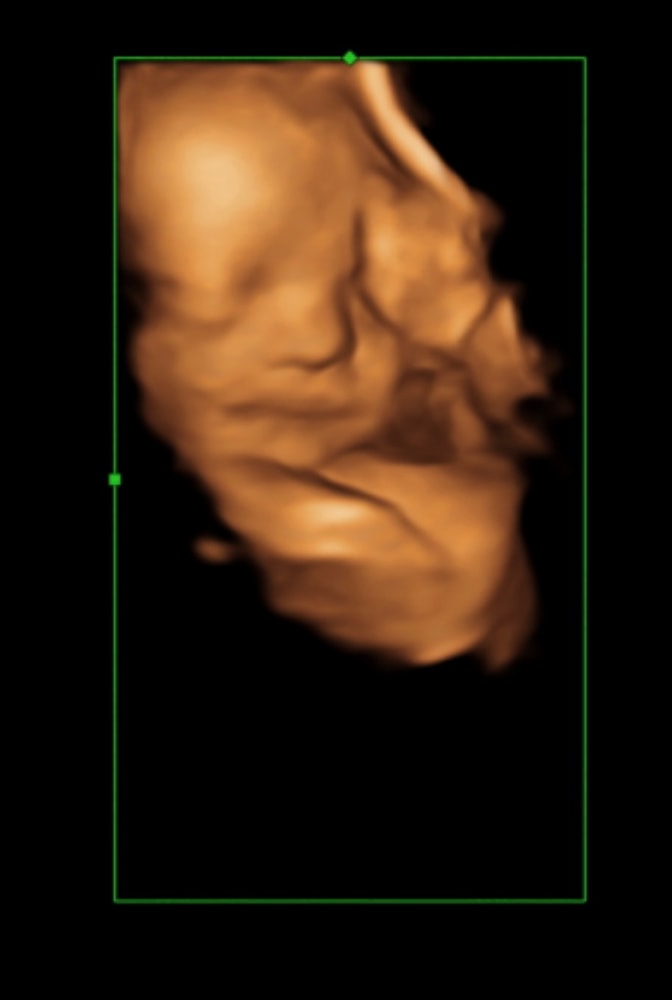

Идем пока ровно 🥰 оба головой вниз . Вес левого - 1148 , вес правого - 1159 . Срок 28,3.

Ну он и ведет себя более ответственно) всегда отвечает на вопросы . А правый молчун